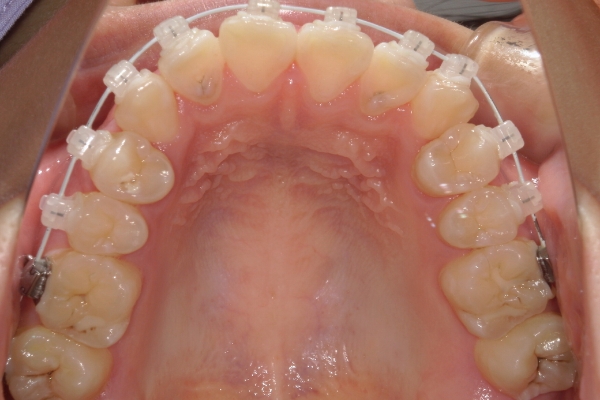

BEFORE

治療前

PROCESS

3か月

AFTER

治療後

骨格的に下あごが前下方に長いことが原因で、受け口、開咬(前歯が当たらない)の症状がでていました。また下あごが右にずれており、その影響で上下の歯列正中(真ん中)の大きなずれも生じていました。顎変形症手術も選択肢の一つでしたが、患者さまの希望もあり、下顎左側小臼歯の抜歯をして通常の歯列矯正で治療をしました。

治療後は、前歯、奥歯の噛み合わせが整い、上下の歯列の真ん中が一致しました。歯列全体のアーチも安定し、機能面・審美面のどちらも大きく改善されました。